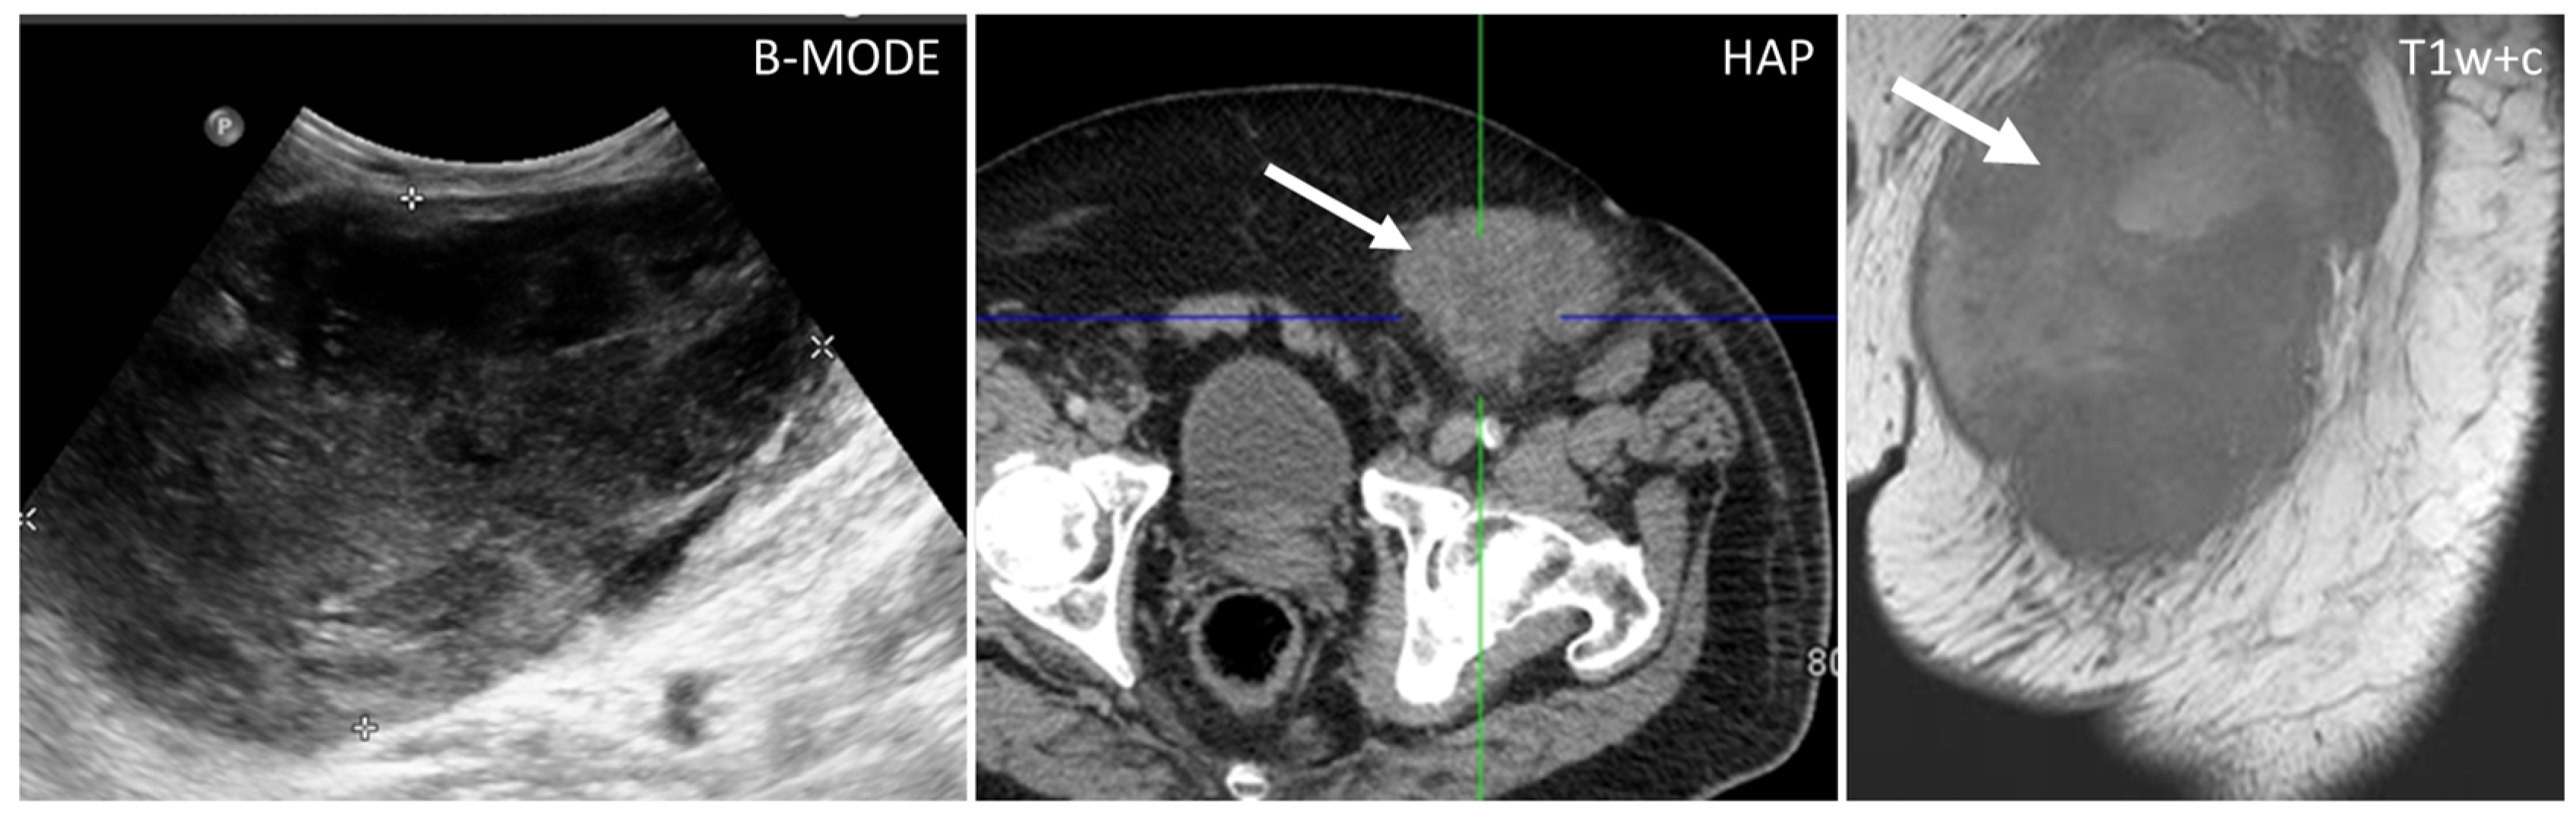

- Leiomyosarcomas: seen on the abdominal wall as either a primary process or as an extension of an intra-abdominal process [23,24]. Leiomyosarcomas demonstrate heterogeneous attenuation and signal intensity, with irregular peripheral enhancement and enhancing solid portions, mixed with hemorrhagic and necrotic areas [24]. Fatty components are absent (Figure 9) [23,24].

- Desmoplastic Small Round Cell Tumor (DSRCT): rare, highly aggressive sarcoma of adolescents, which primarily involves the serosal surfaces of the abdominal cavity infiltrating the abdominal wall [30,31,32]. Classic findings include bulky multiple, hypoattenuating, soft-tissue masses, with omental, serosal, and rectovesical involvement [31,32] and typical punctate or amorphous calcifications [32]. Modest heterogeneous enhancement is seen on arterial phase, without prolonged enhancement or portal washout [31,32] (Figure 10). On MR, DSRCTs are heterogeneously iso- to-hypointense on T1-w images, with hyperintense foci due to intratumoral hemorrhage [32].